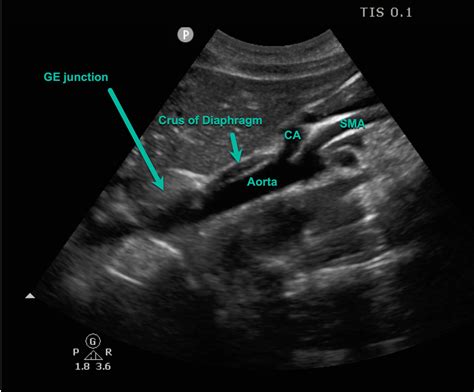

The diaphragm is a thin, muscular partition that separates the thoracic cavity from the abdominal cavity. It is composed of several parts, including the central tendon, the peripheral muscular portion, and the crura. The crura are the muscular extensions that anchor the diaphragm to the lumbar vertebrae. The left crus of diaphragm is one of these extensions, originating from the first three lumbar vertebrae (L1-L3) and extending to the central tendon.

• Computed Tomography (CT) Scan: CT scans provide detailed images of the diaphragm and surrounding structures, aiding in the diagnosis of complex conditions.

• Magnetic Resonance Imaging (MRI): MRI can offer high-resolution images of the diaphragm and its crura, helping to identify structural abnormalities.

• Fluoroscopy: This dynamic imaging technique can visualize the movement of the diaphragm during respiration, helping to assess its function.